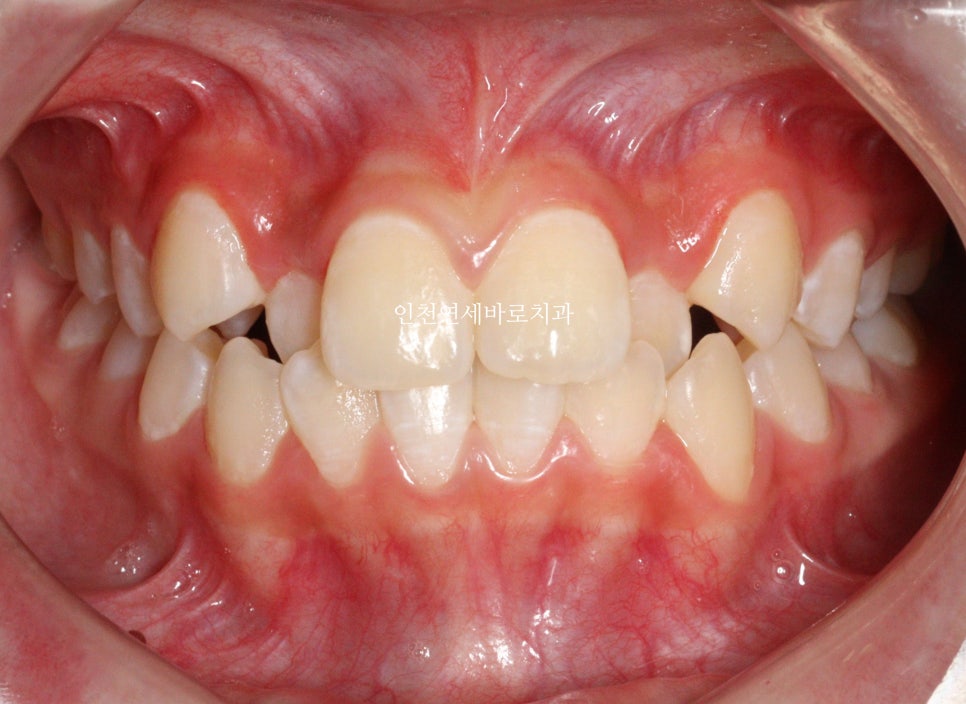

| 주요 증상 | 두번째 치아 덧니 |

2023.4.18.에 처음 내원해서 23년6월초부터 치료를 시작한 아이입니다.

두번째 치아가 덧니로 있는 경우의 치료는 흔한 경우지만

생각보다 많은 노하우가 필요한 치료라고 생각합니다.